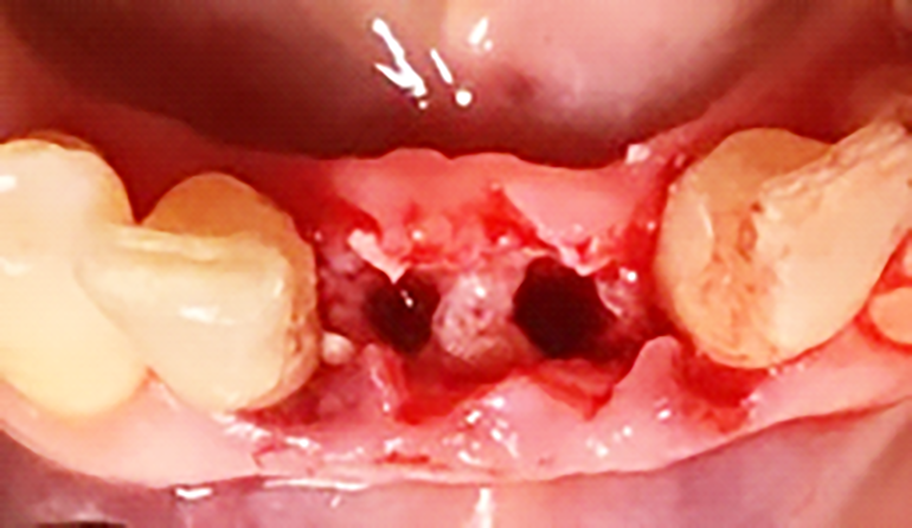

Previa anestesia locale si esegue lo scollamento di un lembo a spessore totale per consentire l’avulsione atraumatica degli elementi 3.1 e 4.1 (figure 1a-1b). Si revisionano le cavità alveolari e si posizionano osso bovino deproteinizzato e una membrana di collagene riassorbibile. Si sutura con filo 5/0, si posiziona un maryland bridge per garantire l’estetica in attesa dell’inserimento implantare e si esegue una radiografia di controllo (figure 2-4).

In seguito all’estrazione degli elementi 3.1 e 4.1 si osserva a una settimana di follow up la perfetta guarigione dei siti (figure 4-5). I successivi follow up mostrano come la rigenerativa abbia ristabilito gli adeguati volumi ossei e grazie all’analisi tridimensionale dei siti implantari è possibile pianificare correttamente il posizionamento degli impianti (figura 6).